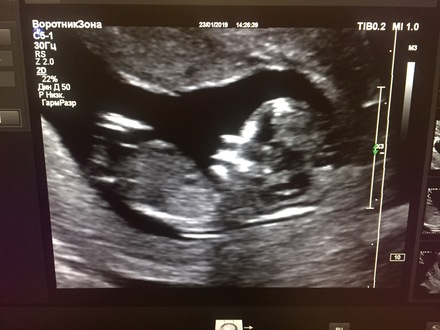

Я тоже с УЗИ... Как же мне понравилось, как Сергей Александрович его проводит!!! Все рассказал, показал. Муж, как завороженный сидел. И у нас прекрасная девочка!!!  так здорово! я тоже дочку третью хочу.. но главное чтобы здоровый!

Девочки , с хорошим узи вас и с доченьками ! Я прошла тоже : все хорошо у нас, носовая кость 1,4, воротниковое пространство 2.1 Пол в ЖК не смотрят . Пойду к Те в понедельник